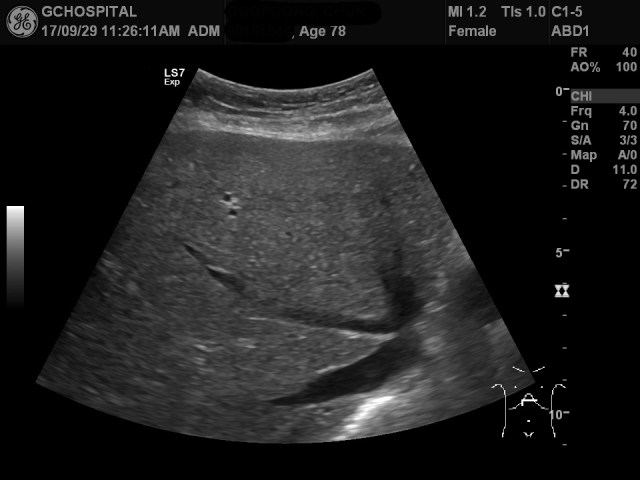

그런데, 간 우엽의 지붕부위는 제대로 확인하지 못한 부분이 존재합니다. 위 영상이 간의 지붕부위를 찍은 영상이지만, 지붕부위의 일부분이 잘려있습니다. 누워있는 자세와 좌측 측와위자세에서 시도해봤지만, 이보다 위쪽을 보는데 어려움이 있었습니다.